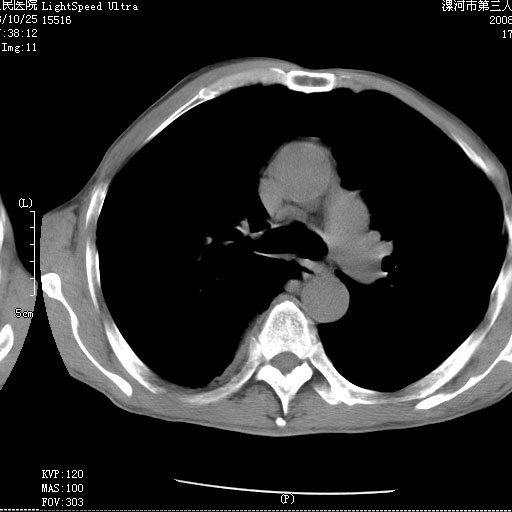

m 老年 发烧、呼吸困难,慢支、肺气肿多年;记的那次是下午大概17:38做的,晚上窒息死亡。

上面的层面就慢性支气管炎肺气肿、肺大泡,别的没有什么、也就不传了。

当时我怀疑:1、阻塞性肺不张早期 2、肺脓肿早期,望老师们发表意见

应该是脓胸的表现,右下肺气管阻塞考虑为痰栓.

你怀疑的有道理,慢支、肺气肿、肺打泡是有了,右下肺的病变有待商议;

首先考虑右下肺炎症并不张,不除外早期肺泡癌改变

病灶边缘清---多个含气小腔---近端未见通畅气管影-----支持-----慢性肺脓肿继发阻塞性肺不张

阻塞性肺不张原因-----脓液未排出

1、右侧脓胸;2、copd;

3、细支气管肺泡癌可以排除,病变以斜裂为界,呈大片状高密度影,内可见多发小气泡,表明有产气杆菌感染所致,内无明显的支气管“枯树枝征”表现,再结合其临床改变(细支气管肺泡癌临表表现重、影像表现轻)所以不符合细支气管肺泡癌(炎症型)的改变。

考虑为右肺下叶支气管痰栓形成并阻塞性肺不张及肺炎。

病变按肺叶分布,病变内可见多个小空腔影,未见充气支气管影,中间段支气管管腔肺窗示密度欠均匀,下肺支气管分叉处基底段支气管隐约可见,未见明显狭窄,中叶支气管通畅,

考虑:阻塞性肺炎伴小脓肿形成可能性大。(痰栓可能性大)

右下肺实变,内有弥漫分面小气泡而无支气管征,叶间裂前移,呈臌大之形,而无收缩之状,兼纵隔稍左行移,故。不支持不张,倒支持大叶肺叶,如楼上所说,小气泡不象残留之肺,不可以考虑产气菌感染吗。

阻塞性肺炎,肺脓肿形成。依据,右下支气管不通,大片实变形内可见小气泡。不支持肺不张。